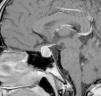

La paciente es remitida a endocrinología pediátrica tras el hallazgo de una cifra elevada de prolactina (198ng/ml, rango de normalidad: 8,5-26,5ng/ml). A la entrevista dirigida, la paciente refiere un año de visión borrosa intermitente y cefalea frontal de 3 meses de duración, acompañado de galactorrea unilateral de escasa cuantía. A la exploración física: talla 169,5cm (DE:+1,1), peso 53,3kg, IMC 19,29kg/m2 (DE:−0,79). Estadio puberal V de Tanner y fenotipo armónico. Ausencia de galactorrea, hirsutismo o acné. El hemograma y la bioquímica general fueron normales, destacando la determinación de prolactina (205,6ng/ml). La resonancia magnética (RM) (fig. 1) evidenció una glándula hipofisaria aumentada de tamaño, con borde superior convexo hacia línea media y aumento de señal sugestivo de cambios hemorrágicos subagudos. La glándula hipofisaria, impronta y oblitera la cisterna supraselar con efecto masa sobre el quiasma óptico. En el estudio oftalmológico se constató una hipermetropía leve, con normalidad en la campimetría y en el fondo de ojo. Con los datos obtenidos se estableció el diagnóstico de prolactinoma con apoplejía subclínica, iniciando tratamiento con cabergolina a dosis de 0,25mg la primera semana y 0,50mg/semana de mantenimiento. Al mes de iniciar el tratamiento, se aprecia en la RM de control (fig. 2), el adenoma con unas medidas de 10×8mm, probablemente sobreestimadas por los signos de sangrado, con una cifra de prolactina de 12,6ng/ml. En la actualidad la paciente presenta ciclos menstruales regulares, visión normal sin cefalea y ausencia de galactorrea.